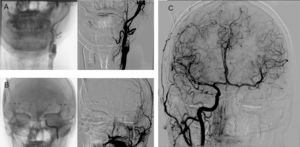

Our patient was a 41-year-old man with a history of locally relapsing squamous cell carcinoma of the nasopharynx; he had previously been treated with surgery, chemotherapy, and radiotherapy, and was admitted electively to our centre for surgical reintervention. Three months before surgery, the patient underwent an angiography-based balloon test occlusion of the carotid artery (200mL of non-ionic iodinated contrast agent were administered), which confirmed that there was sufficient flow compensation by the circle of Willis and the absence of neurological symptoms. The day before the procedure he underwent embolisation of the left internal carotid artery in 2 locations: proximally, beyond the carotid bifurcation, and distally, proximal to the ophthalmic artery (Fig. 1). For the angiography, we used 310mL of non-ionic iodinated contrast. The procedure was uneventful and the patient remained asymptomatic at all times. Renal function was preserved before and after the procedure (glomerular filtration rate >90mL/min) and his arterial blood pressure remained within normal ranges. Six hours after embolisation, the patient presented neurological signs of predominantly motor aphasia, right homonymous hemianopsia, and right facial paralysis. A blood analysis revealed no alterations and the electrocardiography showed sinus rhythm. The baseline sequence of a head CT scan using an iodinated contrast agent (50mL) revealed attenuation of sulci, suggestive of oedema, and cortical contrast uptake in the left hemisphere (Fig. 2A). CT angiography confirmed occlusion of the left internal carotid artery with excellent compensation of intracranial circulation, with perfusion sequences showing no alterations (Fig. 2B-E). In the acute phase, we started antiepileptic treatment with levetiracetam at 1000mg/12h and dexamethasone at 6mg/4h. An MRI scan performed at 24hours showed signal alterations on the FLAIR and DWI sequences in the left parietal and frontal cortex, with no restriction on the ADC map; these findings are compatible with vasogenic oedema. An electroencephalogram revealed slowing of the background rhythm in the left hemisphere. The patient improved clinically, with symptoms resolving 24hours later.

Frontal projections of brain angiography with contrast injection into the left common carotid artery, confirming occlusion of the proximal internal carotid artery (beyond carotid bifurcation) (A) and distal internal carotid artery (proximal to the ophthalmic artery) (B). C) Contrast injection into the right common carotid artery, revealing correct compensation of brain circulation through the anterior communicating artery.